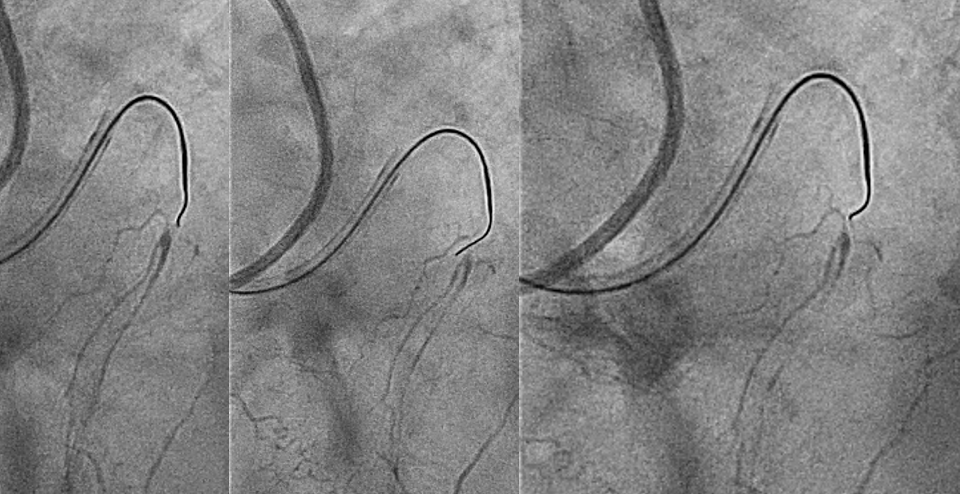

- In the far view, turn the wire towards the target. The far view is the view where the wire is further from the distal cap. We should first choose the far view where the wire is further from the target (Figure 3A) and rotate the wire tip to point toward the target. This is the primary rotation.

- In the near view, turn the wire towards the target with small rotation only. The near view is the angiographic view where the wire is nearer to the distal cap (Figure 3B). In this view, where the wire is nearer to the target, we should rotate the wire slightly towards the target, never more than 40°, and not until the wire faces directly towards the target. This is the secondary rotation. The near view is foreshortened and has significant parallax error; therefore, we should always rotate less than what appears visually correct.

- Return to the far view to wire the distal cap. Although it may seem easier for the operator to wire using the near view, it is always better to wire using the far view due to overlap in the near view.